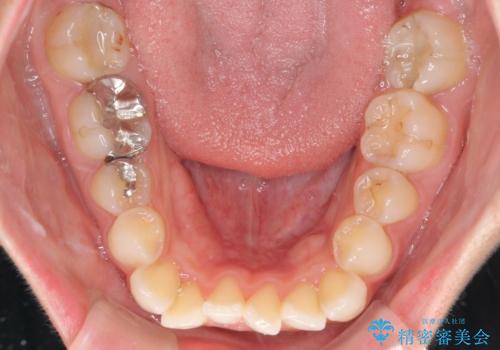

- 前歯のデコボコを気にして来院された患者様です。

主に下顎歯列全体の後方移動とIPR(歯と歯の間を削る)によってデコボコが解消するように設計し、インビザラインにより治療を行うこととしました。

舌突出癖がある方ですと、叢生が解消すると同時に前方に拡大されてしまいますが、ゴムかけをしっかりと行ってくださったこともあり、スッキリとした仕上がりとなりました。